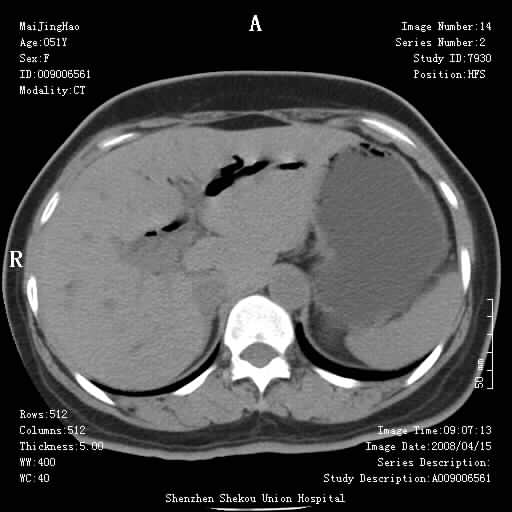

以下是引用yangyudong333在2008-4-26 6:17:00的发言:[br]1胆系感染,可能为金葡菌感染,2考虑有化脓性胆管炎致胆总管扩张,3胰头部增大,建议做增强

以下是引用liangshusheng在2008-4-26 12:34:00的发言:[br]11年前做的手术现在还有积气,可能吗?还是考虑有胆管炎产气,胰头部增大,建议做增强

以下是引用听蝉观竹在2008-4-26 14:21:00的发言:[br]这个病例许多人认为“胰头增大”,那么到底胰头增大的标准是什么呢?

以下是引用听蝉观竹在2008-4-27 10:10:00的发言:[br]关于胰头大小问题有几种测量方法和正常值:[br][br]1、直量法:横径<4cm;[br]2、胰头横径与相邻层面椎体横径的比值为二分之一,超过椎体横径就提示胰头增大;[br]3、正常组成年人肠系膜上动、静脉水平夹角正常值范围为4.9°~34.7°大于35°提示胰头增大。[br][br]上述方法只是一种具体的判断,是“量”的评估,更重要的是“质”的评估:一是观察边缘是否光滑,有无局部隆起,有无分叶;二是观察密度(增强,尤其在动脉期和门脉期)是否均匀。[br][br]所以对于胰头是否有异常不仅仅是是目测可以解决问题的,不要轻易就说“胰头增大”。还有一个问题就是测量胰头应该在增强ct上进行,这样可以避免将血管测量进去。[br][br]为什么啰嗦讲怎么多,因为我们实际工作中同样存在影像科医生和临床医生动不动就说胰头增大,说是胰头癌。大家看看是不是这种情况?[br][br] 我个人观点-----本病例的胰头不增大。[br][br][本贴已被 听蝉观竹 于 2008-4-27 10:12:41 修改过]